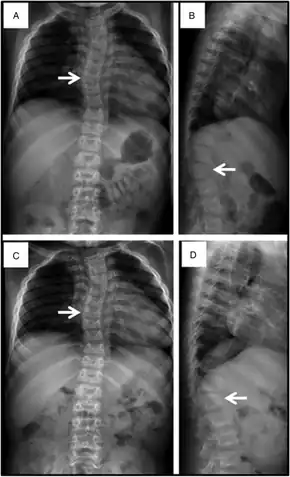

Mucopolysaccharidosis VII - a & c) Reveal mild scoliosis arrow and broad ribs, b & d) demonstrate irregular anterior vertebral body growth